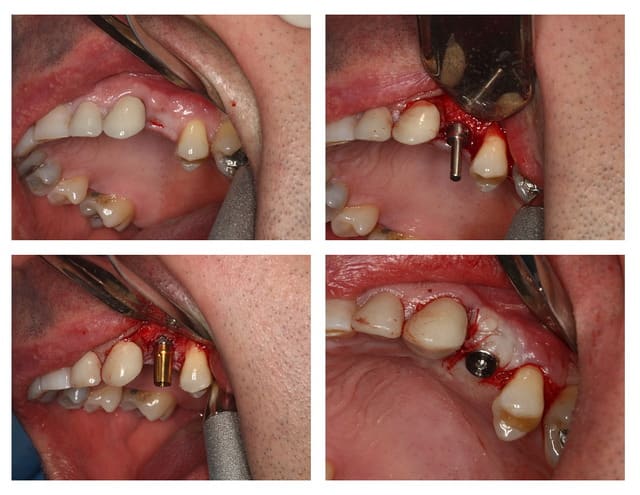

Allez, pour apporter mon caillou à la plage, un cas intéressant, d'implant en urgence.

consultation suite à une chute et fracture de 21 couronnée, un 29 Décembre, décision de poser l'implant le 31.12.

Extraction, mise en place d'un implant de 5*11.5 torque > 35N

Mise en place d'une dent provisoire transvisée.

Prothèse transvisée définitive à 3 mois.

Les 2 dernières photos à 1 an.

la photo ceram en place est à 6 mois. Noter l'amélioration des papilles entre 6 mois et 1 an...

non pas comblé pourtant hiatus assez important environ 1.5mm.

Longueur 11.5, mais j'aurais du mettre un plus long, pour la MCI j'aurais pris moins de risque...